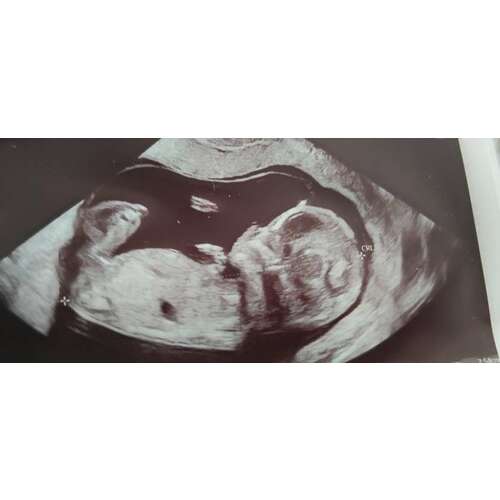

Onder de beentjes lijkt beetje opgezwollen.. precies 2 tegen elkaar bij een jongetje zie je een balletje eronder dan

Daar zie je precies een piemeltje en een balletje, is mijn echo, weet ook nog niet 100% zeker maar dat maken ze mij wijs Hahaha 😅🙈

Staat inderdaad ook omhoog, dus een jongen!

Echt overduidelijk een jongen hoor haha! Onwijs leukkk❤️😍